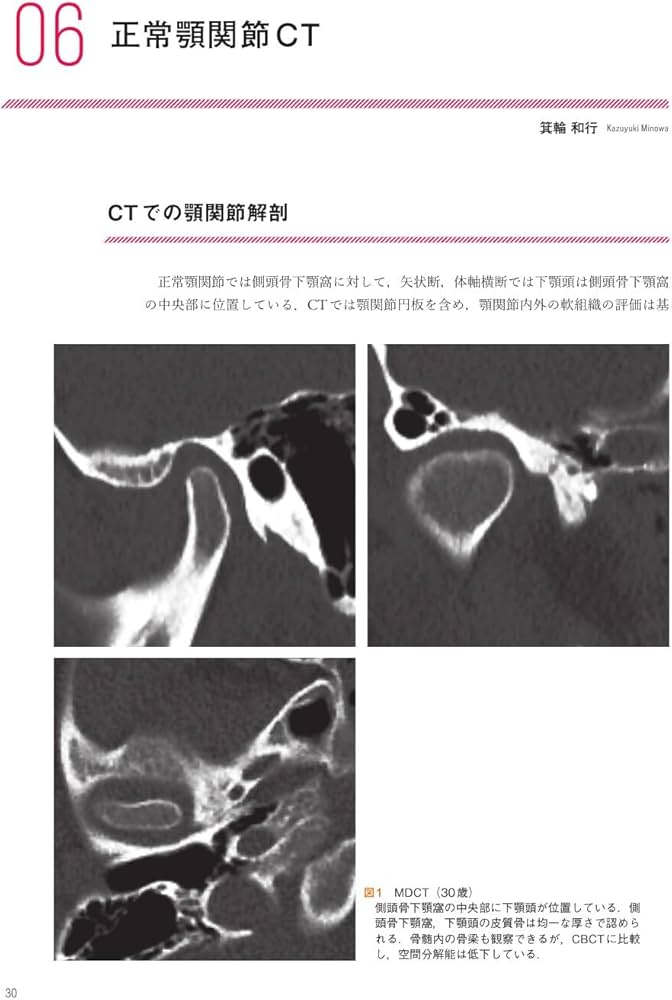

【裁断済み】「顎関節の画像診断 : 臨床医によるMRI・CT読像の手引き」大谷 昌 / 鷹木 雪乃 / 箕輪 和行 / 箕輪 和行 / 月岡 庸之 / 金田 隆 / 金田 隆 / 阿部 伸定価: ¥ 10000#大谷昌 #大谷_昌 #鷹木雪乃 #鷹木_雪乃 #箕輪和行 #箕輪_和行 #箕輪和行 #箕輪_和行 #月岡庸之 #月岡_庸之 #金田隆 #金田_隆 #金田隆 #金田_隆 #阿部伸 #阿部_伸 #本 #自然/医療・薬学・健康本文に書き込みなし。値下げできません。素人検品、素人保管です。ローラー痕や、上下面、ページ端に汚れなどがある場合があり、ご容赦願います。あくまで中古品のため、神経質な方はご遠慮ください。